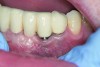

Following active therapy, probing depths of 4 mm or less (Figure 1 and Figure 2) and the absence of bleeding on probing contribute to improved health and stability. Increasing probing depths should alert the therapist to identify etiology and determine whether active periodontal therapy is warranted. The absence of bleeding on probing is a strong predictor of stability, and although the presence of bleeding does not always result in attachment loss, it remains an important parameter to evaluate.14 Bleeding on probing is also an important parameter for assessing implant health during maintenance. Serino et al15 evaluated 27 patients with 19 dental implants over 5 years. Patients were seen every 6 months and they concluded that bleeding on probing was a good predictor for attachment loss and disease progression around the implants (Figure 3).

Fig 3. Bleeding on probing and increasing pocket depths around implant sites indicates a need for treatment.

Figure 3